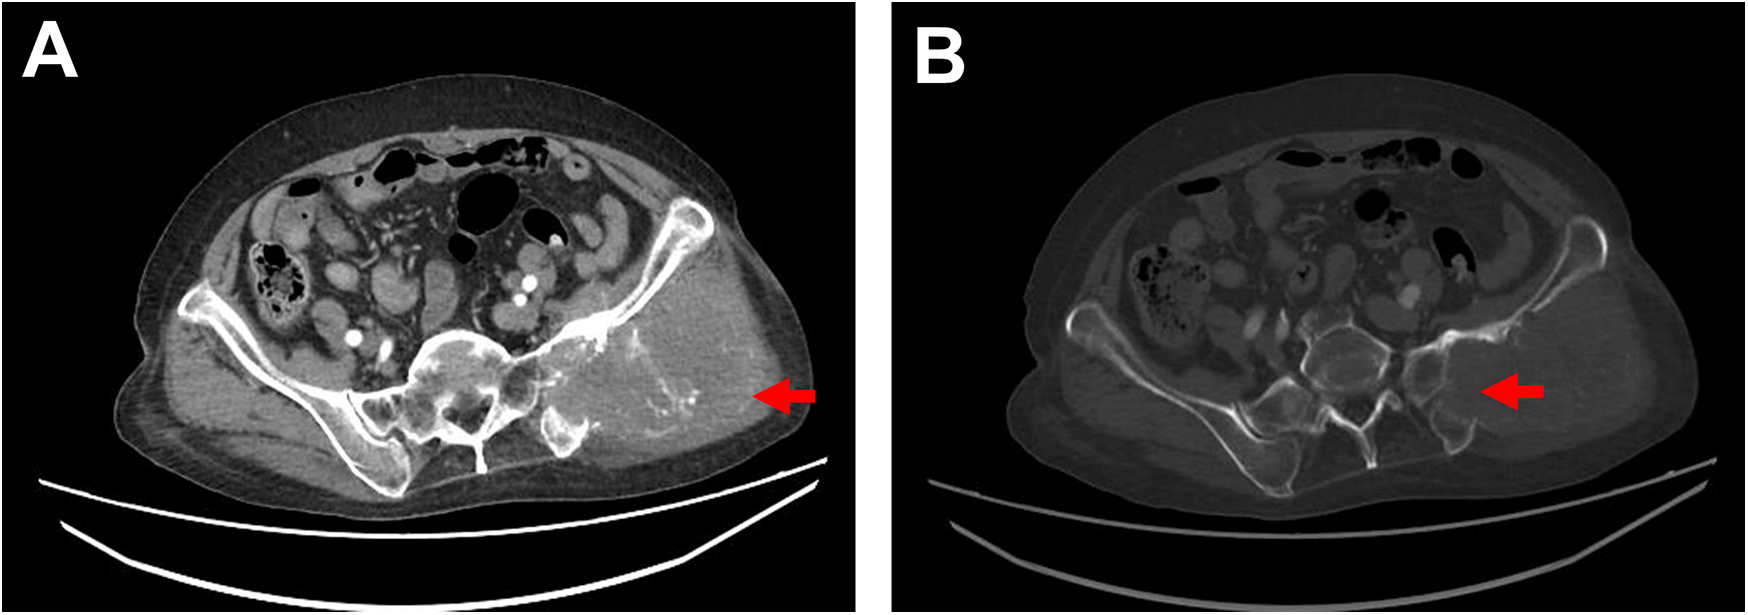

Physical examination: The patient's general condition was stable, with a hard mass palpable in the left hip, approximately 9 cm × 9 cm in size, fixed, and tender. Blood test: D-dimer level was 6.13 mg/L. Chest and abdominal CT conducted on July 5, 2024 revealed a soft tissue mass in the left hip involving the sacrum and iliac bone, consistent with the appearance of a malignant tumor (Figures 1A,B); a filling defect in the thoracic aorta suggested a possible tumor.

Figure 1

Ct imaging. (A) Contrast-enhanced CT shows a soft tissue mass in the left hip measuring approximately 10 cm × 9 cm, with irregular margins, locally involving the sacrum and ilium, accompanied by bony destruction of the sacrum and ilium, as indicated by the red arrow. (B) Bone window view displays bony destruction of the sacrum and ilium, as indicated by the red arrow.